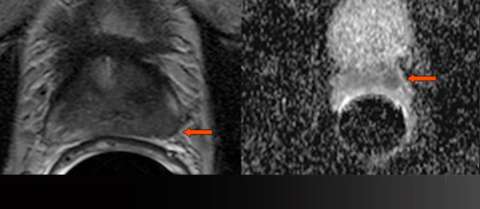

LEFT: Axial T2-weighted image: low signal bulges the capsule (arrow)

RIGHT: Gray-scale apparent diffusion coefficient (ADC) map: focal restricted diffusion (arrow)